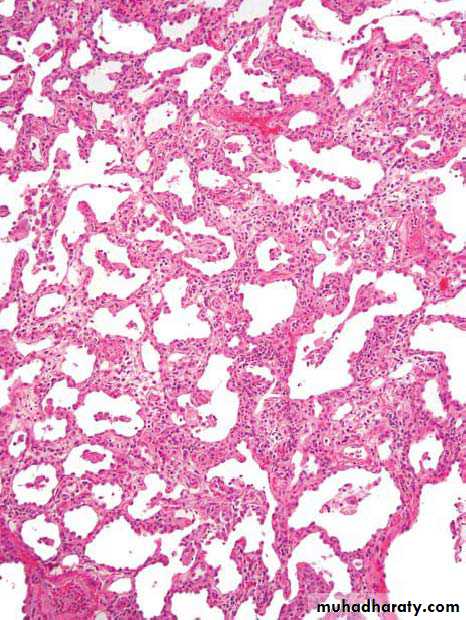

The fibrotic and inflammatory process within alveolar walls; this is the characteristic finding in atypical pneumonia